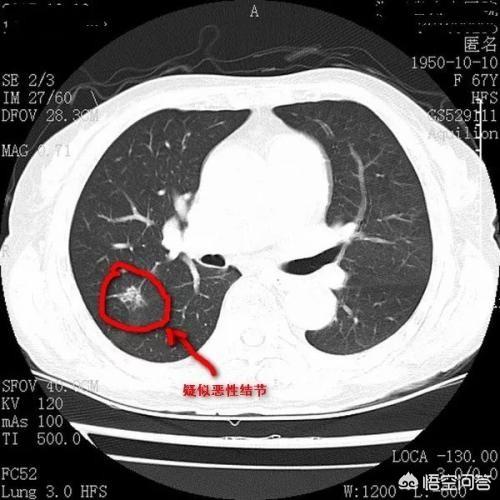

Der Pfeil zeigt auf den Knoten, der sehr klein war, als er im März 2016 entdeckt wurde, etwa 0,5 cm, und jetzt werden bei Routineuntersuchungen sehr viele Knoten wie dieser entdeckt.Es gibt keine Möglichkeit, auf den Bildern festzustellen, ob es gut- oder bösartig ist, sondern nur die Möglichkeit der Überprüfung, und die Überprüfung und Nachsorge ist auch das beste Mittel.

Sieben Monate später, bei der zweiten Nachuntersuchung im Oktober 2016, wurde deutlich, dass dieser Knoten größer und runder geworden war. Der vergrößerte Knoten bei der Nachuntersuchung sollte auf die Möglichkeit einer Bösartigkeit hinweisen, aber dieser Patient entschied sich dennoch nicht für eine Operation.

Nach weiteren 1 Jahr und 2 Monaten, die dritte Überprüfung im Dezember 2017.Sie können sehen, dass dieser Knoten ist viel größer als zuvor, die bösartigen Zeichen sind lobulierte aus und es hat sich im Inneren fest, diese Zeichen diagnostizieren die Lunge Krebs im Grunde, aber der Patient immer noch nicht haben Chirurgie.

Nach einem weiteren Jahr, bei der vierten Untersuchung im Januar 2019, hatte sich der Knoten in eine Masse (>3 cm) verwandelt, und dieses Lungenkarzinom war lehrbuchmäßig, mit im Grunde allen Anzeichen einer Bösartigkeit, die für Lungenkrebs sprechen.Unregelmäßige Ränder, Läppchen, Grate und Anzeichen von Pleuraziehen.

Glücklicherweise wurden noch keine Metastasen festgestellt, und eine chirurgische Entfernung ist immer noch möglich. Wenn eine Behandlung noch nicht in Frage kommt, kommen Sie in einem Jahr zur Nachuntersuchung, und Sie können mit zahlreichen metastatischen Veränderungen rechnen. Bei der zweiten Nachuntersuchung wurde festgestellt, dass die Läsionen größer waren, so dass zu diesem Zeitpunkt eine chirurgische Resektion hätte durchgeführt werden müssen, ohne dass es zu einem Rezidiv oder einer Metastasierung gekommen wäre. Wenn die Läsion größer wird, können sich jetzt Krebszellen im Blut befinden, und dann ist das Risiko eines Rezidivs und einer Metastasierung höher.